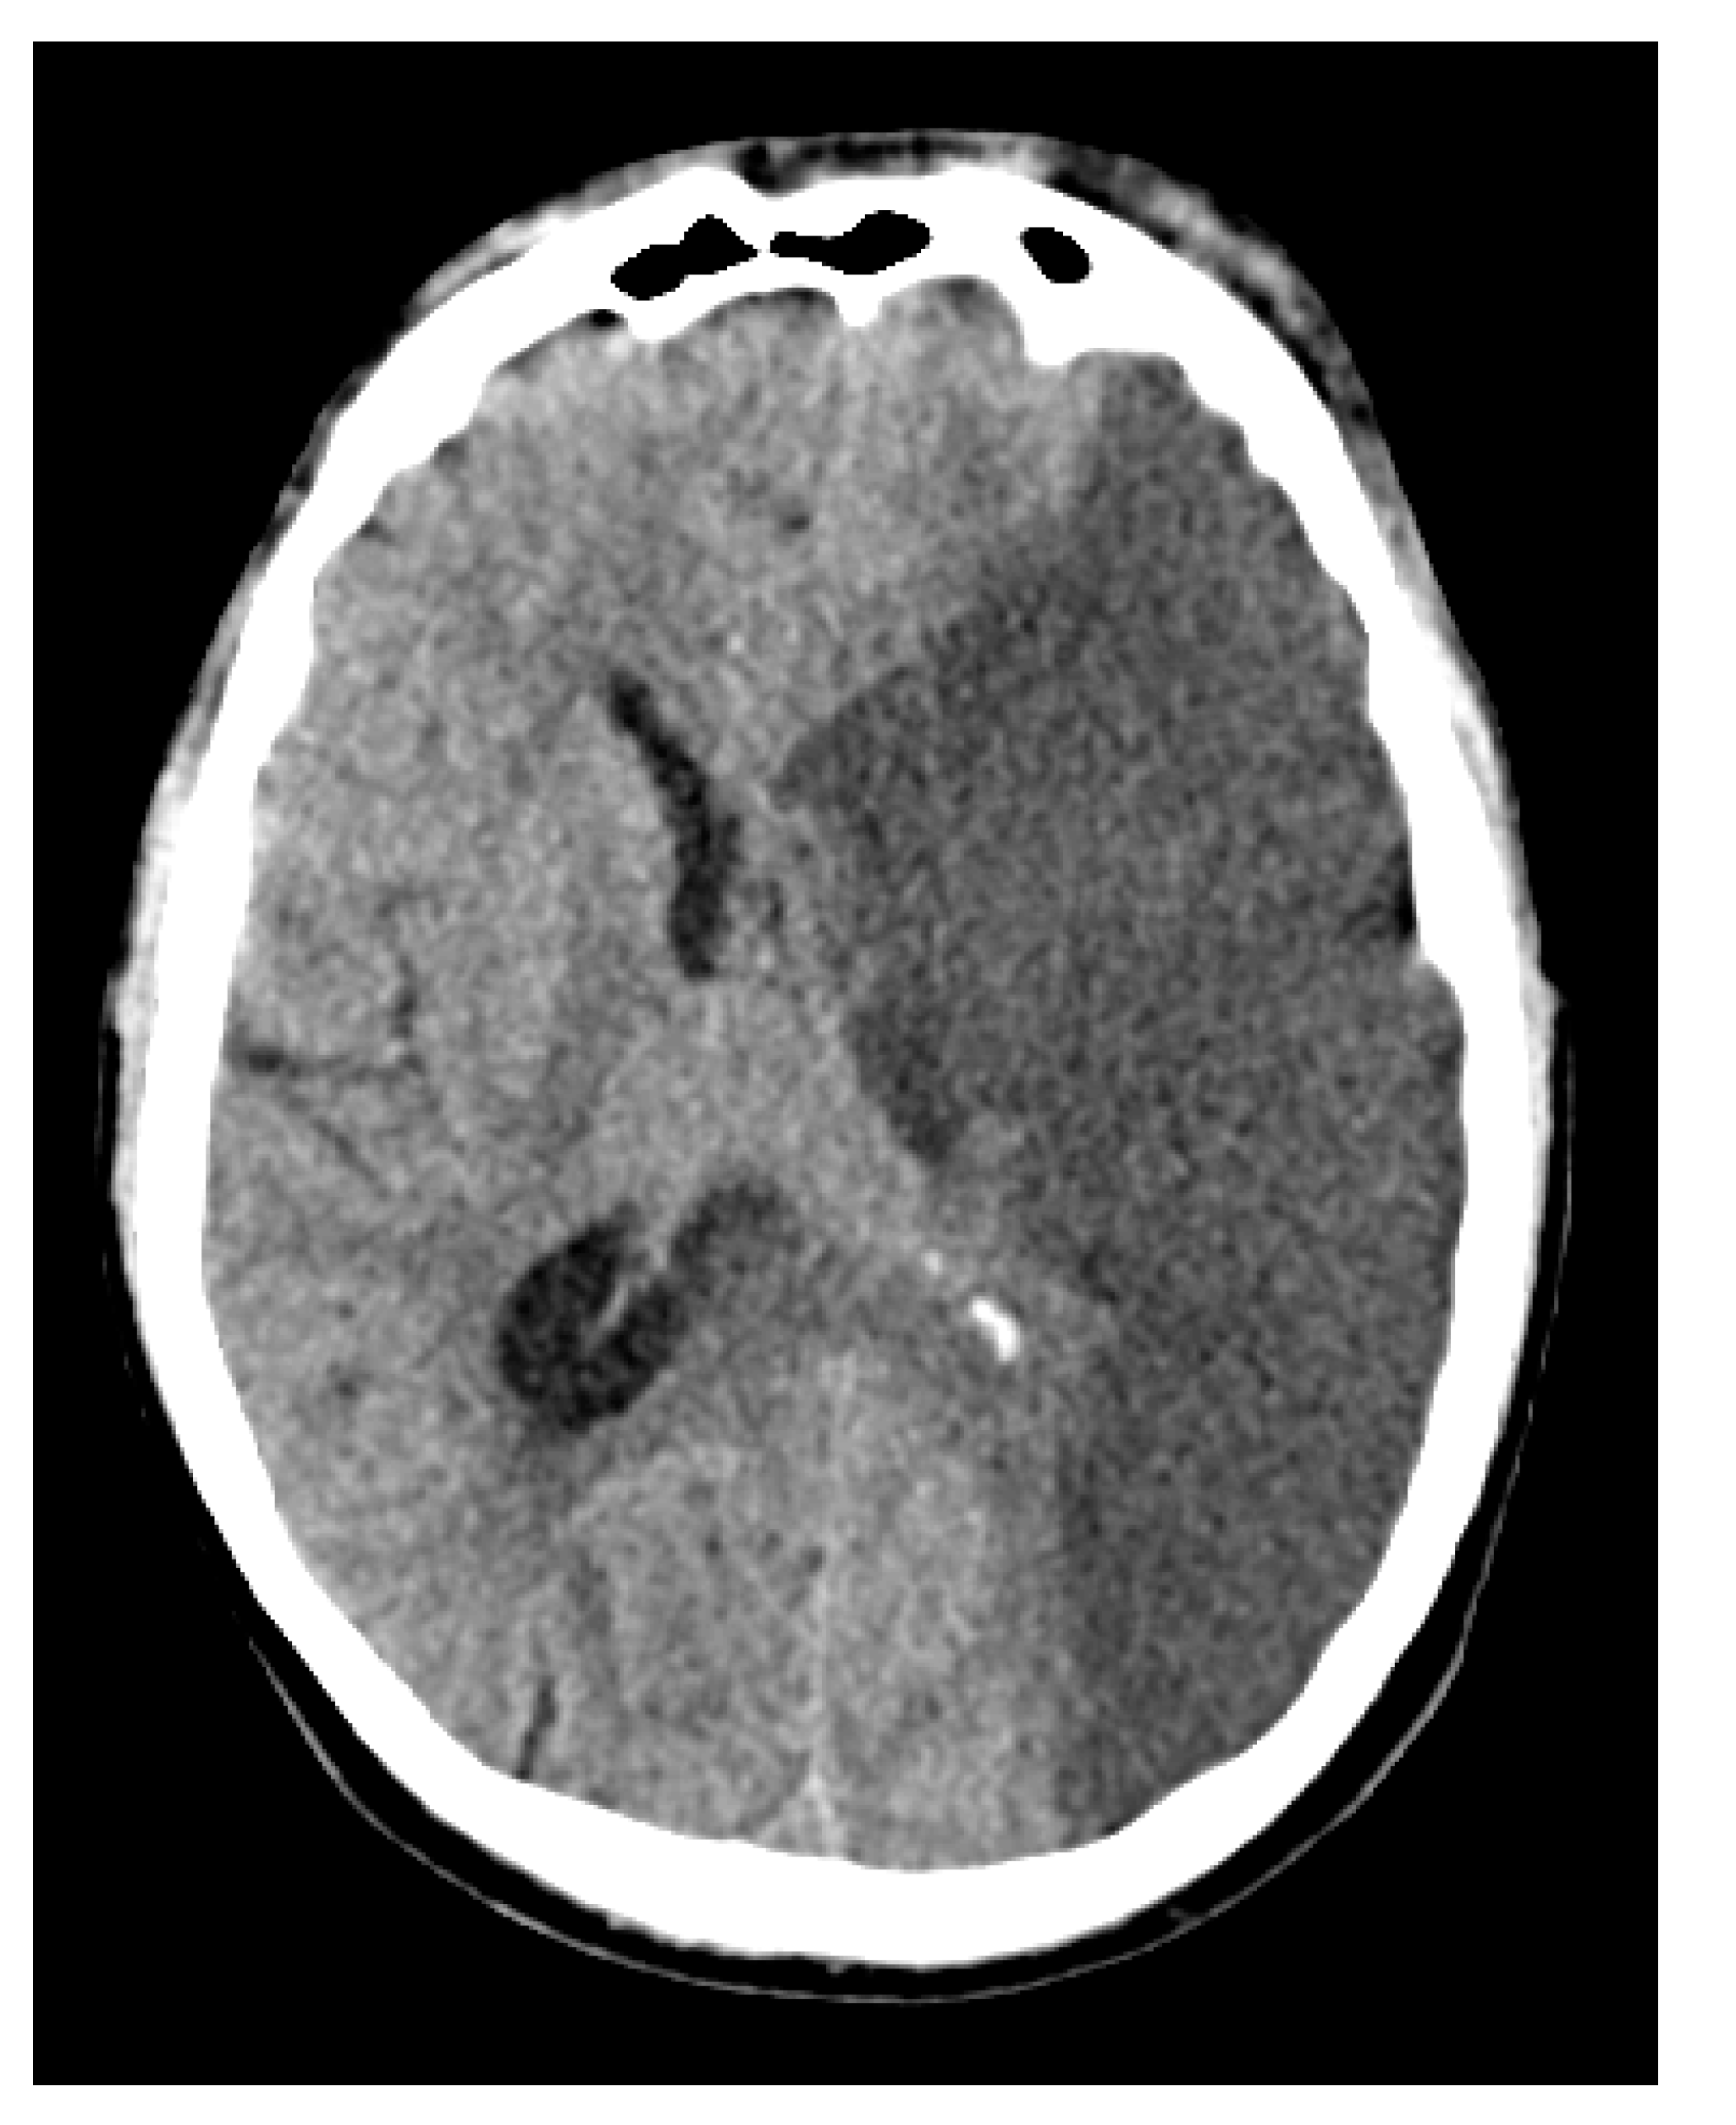

Figure 7.

Non-contrast CT scan of the head demonstrating a hypodense area in the left middle cerebral artery territory, indicative of malignant media infarction. The left lateral ventricle is partially compressed, and there is a midline shift of 1–2 cm to the right, suggesting mass effect due to the infarction. No hemorrhagic transformation is seen.